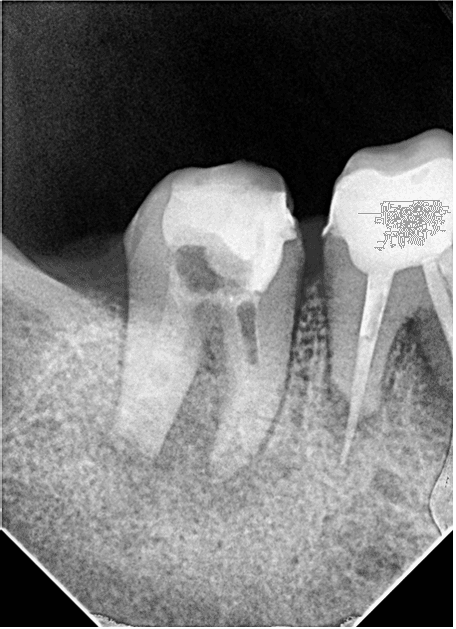

Kırık eğenin etrafından ultrasonik uç ile preparasyon yapılmaya çalışıldı ancak eğenin apikalde duvarla teması olmadığı ve tamamen granülasyon dokusu içerisinde olduğu anlaşıldı (RESİM 3).

Resim 3: Kırık eğenin granülasyon dokusu içerinde kayboluşu

Daha sonra kontrol röntgeni alındı ve eğenin konumu tespit edildi (RESİM 4).

RESİM 4: Kırık eğenin ve taşkın gutanın kök ucundan apikale ilerlediği tespit edildi